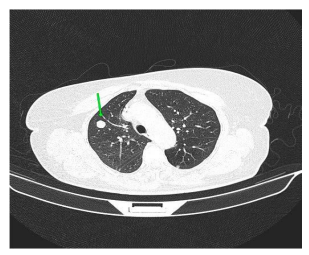

On palpation, there was an 8cm nodule in the right breast and mobile and fibroelastic axillary lymph nodes. There were no palpable nodules in the cervical or supraclavicular region bilaterally. A core needle biopsy was performed with an anatomopathological result of triple-negative grade 2 adenoid cystic carcinoma. Staging demonstrated two 1.1cm pulmonary nodules with soft tissue density suggesting metastasis. Abdominal tomography demonstrated liver nodules suggestive of secondary implants. The PET scan confirmed uptake in the lung and liver nodules, in addition to lytic lesions in S3. Liver biopsy confirmed implantation of adenoid cystic carcinoma. The patient was staged as T2N0M1. Chemotherapy was started with a regimen of Carboplatin, Paclitaxel and Pembrolizumab. After the third cycle of chemotherapy, the breast was reevaluated without showing any tumor reduction. The metastases also did not regress, and treatment was interrupted. The patient evaded the service until he returned in January 2024 complaining of pain in his right hip and difficulty walking. Chest and hip tomography showed an increase in lung lesions and the appearance of lytic metastasis in the iliac bone (figure 1, 2, 3).

Figure 1: